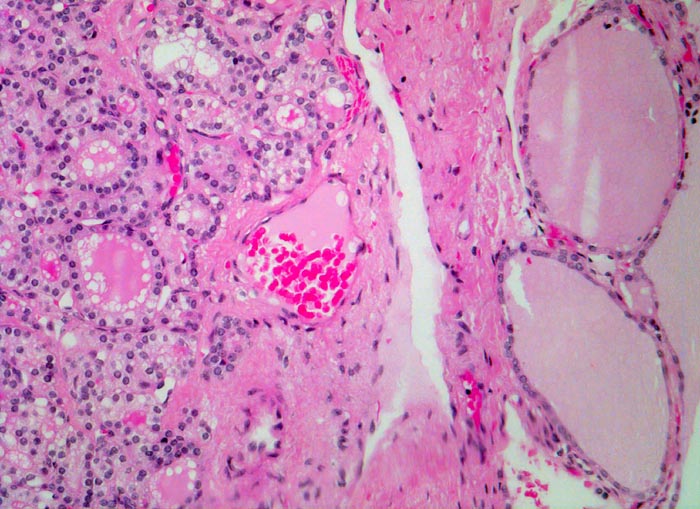

- Kompression des angrenzenden Schilddrüsenparenchyms. Dieses besteht aus grossen Follikeln mit kubischem oder abgeflachtem Epithel und reichlich kompaktem dunklem Kolloid in den Follikellumina.